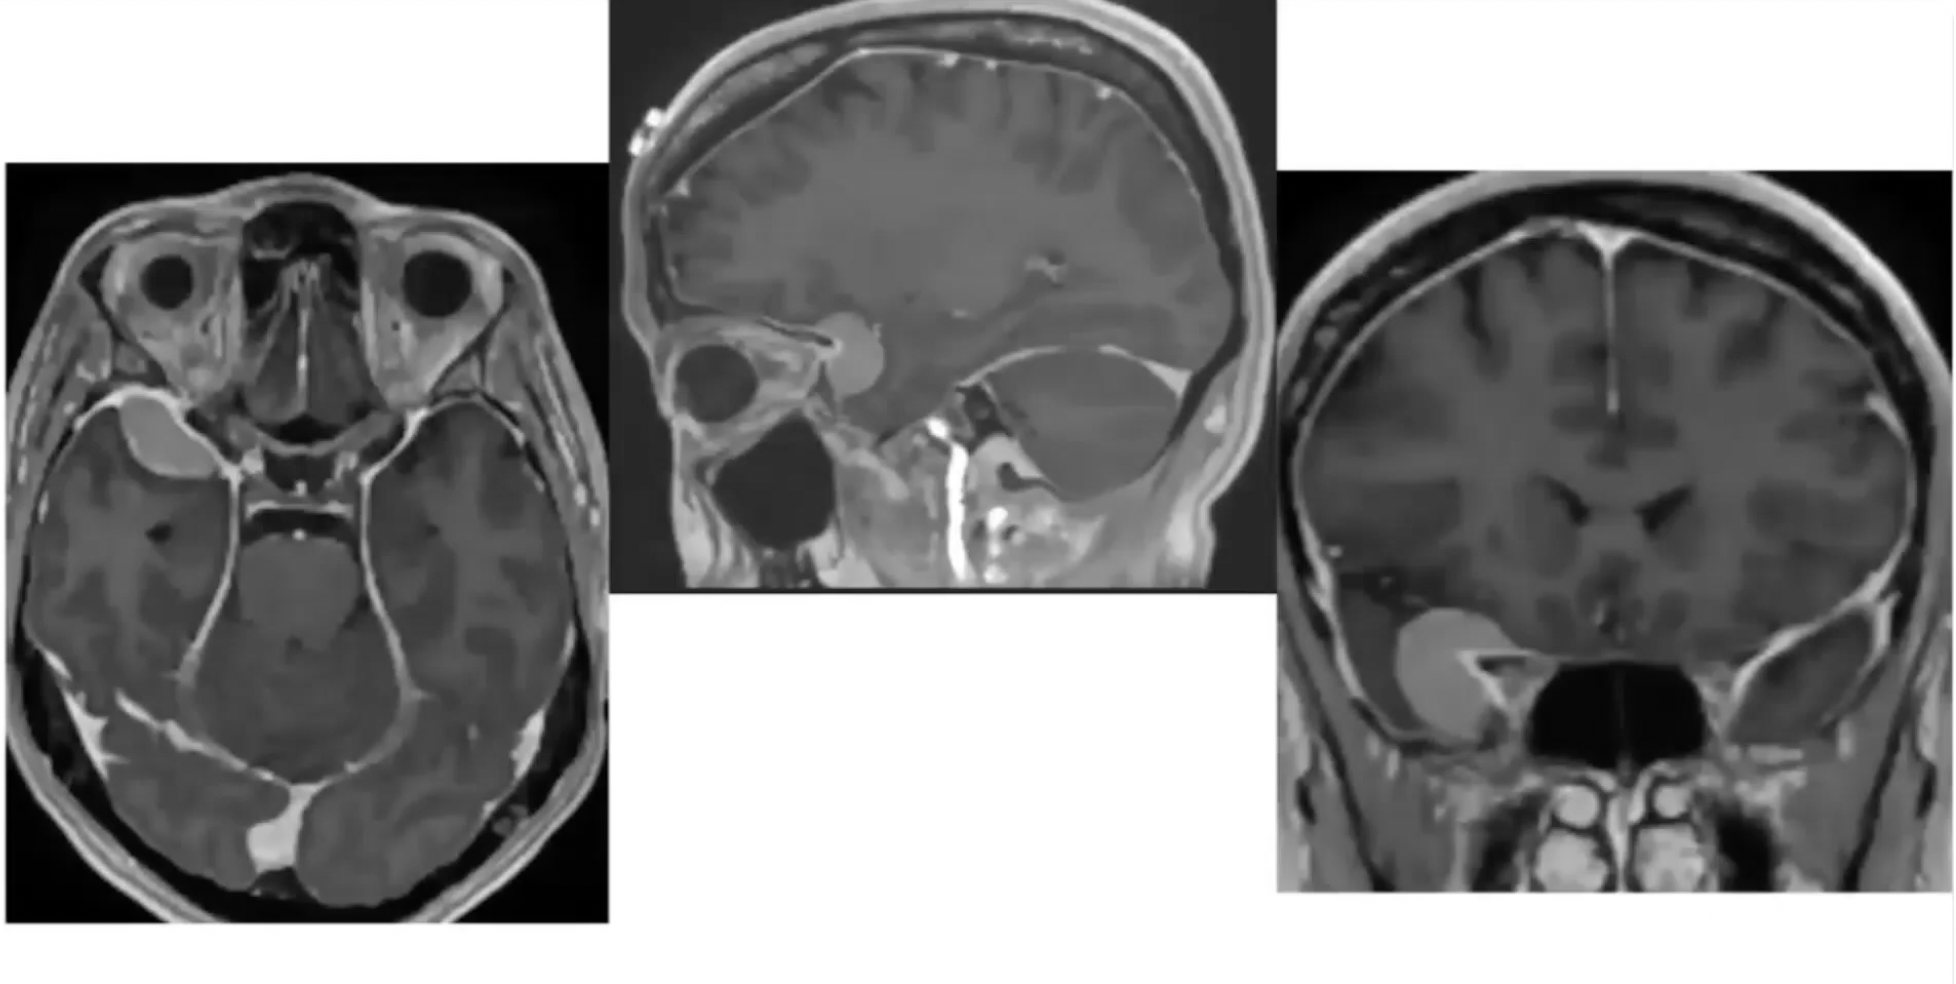

A purely endoscopic endonasal approach was used to remove suprasellar lesions in a series of 10 patients. Five lesions were prechiasmal (three tuberculum sellae and two planum sphenoidale meningiomas) and five were post-chiasmal (four craniopharyngiomas and one Rathke cleft cyst). The floor of the planum sphenoidale and the sella turcica was reconstructed using a multilayer closure with autologous and synthetic materials. Spinal drainage was performed in only five cases. Complete resection of the lesions was achieved in all but one patient. The pituitary stalk was preserved in all but one patient, whose stalk was invaded by a craniopharyngioma and who had preoperative diabetes insipidus (DI). Vision improved postoperatively in all patients with preoperative impairment. Six patients had temporary DI; in five, the DI became permanent. Four patients with craniopharyngiomas required cortisone and thyroid replacement. After a mean follow up of 10 months, there was only one transient CSF leak when a lumbar drain was clamped prematurely on postoperative Day 5.